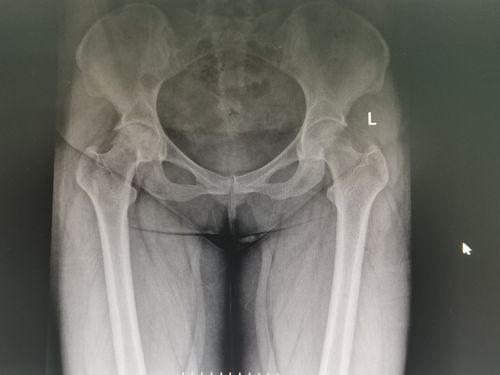

dr片示:右侧股骨头形态完整,内密度不均匀,可以多发斑片状低密度影,髋